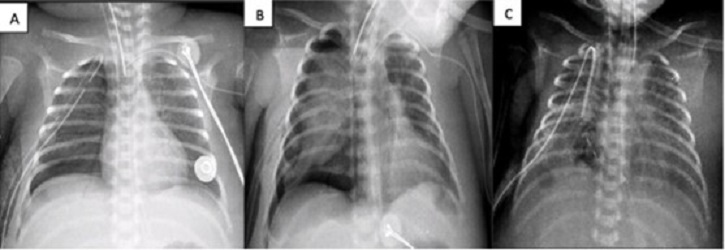

Figure 2

A) Chest x-ray before pleurodesis. B) Chest x-ray 24 hrs post-pleurodesis. C) Chest x-ray 48 hrs post-pleurodesis.

A 16-day-old male baby, born at 39 GW (3500 g) (S/P left diaphragmatic hernia repair and chest tube removal at day 15), developed left-sided tension pneumothorax. It was managed with ventilatory support on SIMV with FiO2 at 35%, and chest tube placement. PAL was encountered for more than 7 days. ABPP was performed and improvement was noted at 24 hours (no bubbles, radiographic improvement, and decrease in ventilatory parameters). The chest tube was removed on the 19th day of life (Fig. 2)